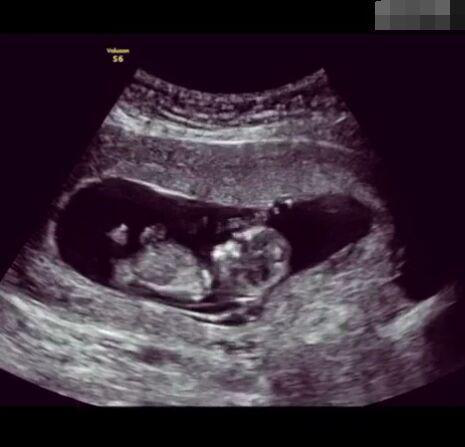

孕育生命是一件無(wú)比非凡的事!想像一下,我們都是從一個(gè)肉眼難見(jiàn)的小小受精卵發(fā)育而來(lái),而這只需要一顆卵子與一顆精子的結(jié)合,就能實(shí)現(xiàn)一個(gè)生命的從無(wú)到有的過(guò)程,這是多么神奇的一件事情!

懷孕后,寶寶的性別一直是全家人的重點(diǎn)關(guān)注對(duì)象。而男女性別的差異,在基因?qū)用骟w現(xiàn)在第二十三對(duì)染色體上,如果是XY則是男孩,XX則是女孩,這都是由那枚與卵子結(jié)合的精子來(lái)決定。

那些做了B超檢查確定胎兒男女,生下來(lái)后發(fā)現(xiàn)不對(duì)的,多半是因?yàn)樵贐超檢查時(shí)寶寶太調(diào)皮,以致影響了檢查準(zhǔn)確性。就比如說(shuō),有的女寶寶在媽媽肚子里玩自己的臍帶,把臍帶夾到了兩腿中間,B超就有一定幾率拍出來(lái)好像是男寶寶的特征,導(dǎo)致被誤認(rèn)為是男孩子。還有些男寶寶過(guò)分害羞,在做B超時(shí)雙腿緊緊并攏,醫(yī)生也很難判斷男女,只好大致猜測(cè)是女孩,就又造成了誤會(huì)。因此,B超亦不是萬(wàn)能的。